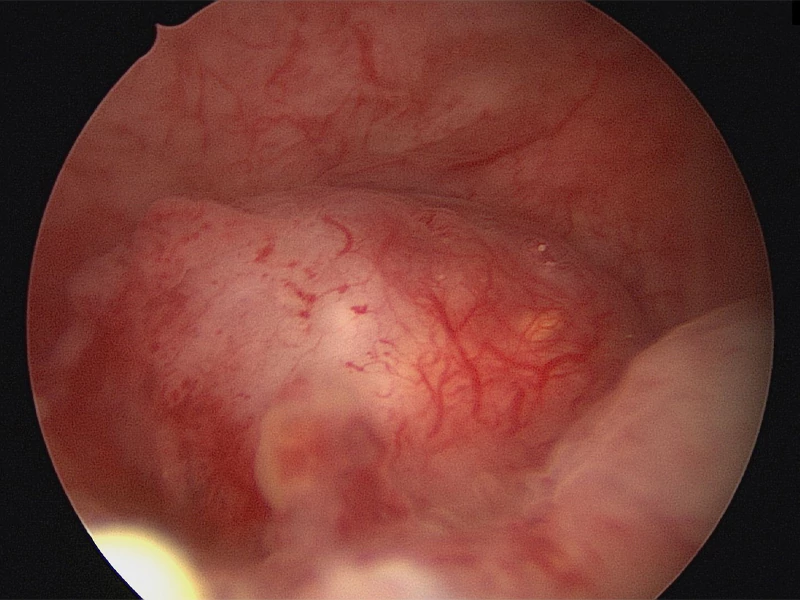

هیستروسکوپی رحم در تبریز؛ تشخیص دقیق و درمان بدون درد

هیستروسکوپی رحم روشی برای مشاهده و بررسی کامل داخل رحم محسوب میشود. بیماریهای زنانه مانند آندومتریوز و کیستها معمولا در رحم رخ میدهند و میتوانند